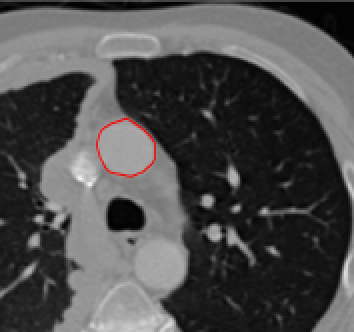

Test 3 – Further Results from the Geodesic Model M7. In this test we give some medical segmentation results obtained using the Geodesic Model M7. The results are shown in Figure 14. In the final two columns we use anti-markers to demonstrate how to overcome blurred edges and low contrast edges in an image. These are challenging and it is pleasing to see the correctly segmented results.